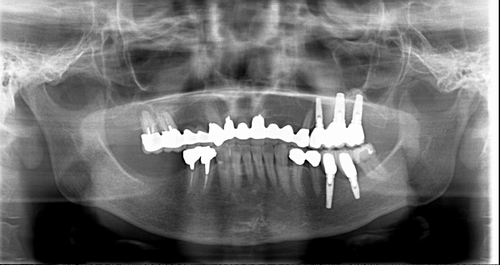

この患者様は、右上の奥歯の歯茎から出血してくるとのことで来院されました。歯周組織検査とレントゲンで診断を行った結果、重度の歯槽膿漏が認められ、保存不可能の為、抜歯になると伝えたところ、入れ歯は絶対に嫌だと言われたので、インプラント治療となりました。CT撮影を行ったところ、上顎洞底までの距離が3ミリ程度しかなかったのですが、骨が固く、フィクスチャーの一次固定が良好だったので、開窓法による上顎洞底挙上術とフィクスチャーの埋入を同時に行いました。約10カ月後に二次手術を行い、上部構造をセットしました。また、右下の臼歯部のブリッジにも大きな二次カリエスが認められ、7番の遠心根が抜歯になり、6番、7番にインプラント治療をしました。

■術前パノラマ